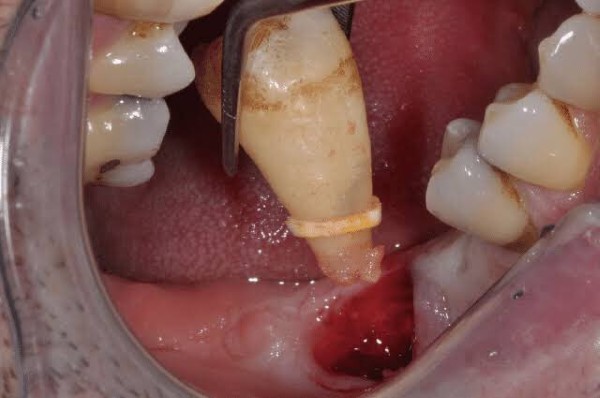

Lỗ sau khi nhổ răng khôn là một khoảng trống sinh lý tại huyệt ổ răng, hình thành ngay sau khi chân răng được bác sĩ tách khỏi cấu trúc xương hàm và mô nướu. Trong lĩnh vực hậu phẫu nha khoa, đây là một phần tất yếu của quá trình lành thương mô mềm và tái tạo xương, đóng vai trò như một “buồng đệm” để cơ thể bắt đầu cơ chế tự phục hồi.

Việc hình thành lỗ trống bắt nguồn từ các chỉ định nhổ răng lâm sàng khi răng khôn mọc lệch, mọc ngầm hoặc mọc kẹt gây áp lực tiêu cực lên các răng lân cận và làm xô lệch cấu trúc toàn hàm. Dưới đây là những nguyên nhân phổ biến dẫn đến sự hiện diện của lỗ sau khi nhổ răng:

Độ phức tạp của tiểu phẫu: Những ca nhổ răng khôn mọc ngầm, phải cắt xương hay chia chân răng sẽ gây tổn thương mô lớn hơn, từ đó đòi hỏi thời gian phục hồi lâu hơn.